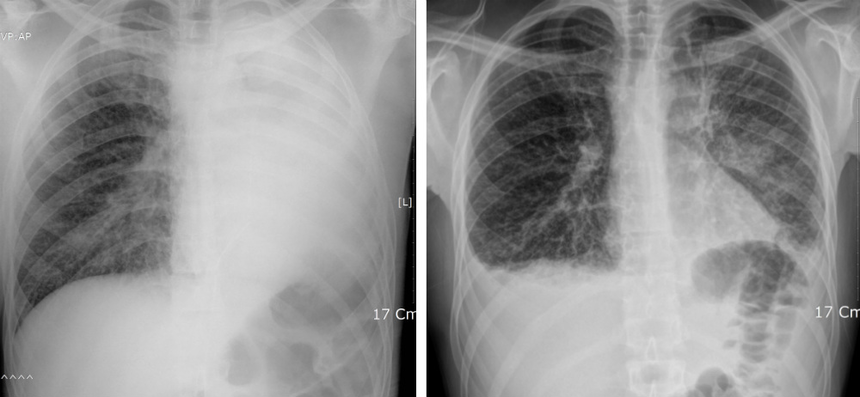

(왼쪽)폐암 4기 환자의 좌측 폐암으로 기관지가 완전히 막혀 무기폐(팽창된 상태를 유지하지 못하고 쭈그러든 상태)가 발생했다. (오른쪽) 면역 항암제와 기존 화학 항암제를 병행한 뒤 폐암의 크기가 작아지면서 좌측 기관지가 열려 무기폐가 사라졌다. (강동경희대병원)​